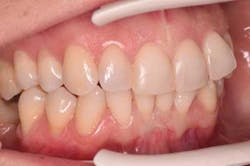

Because of her high-stress job and infrequent use of her night-guard, clenching and bruxism habits were reflected in her dentition. In addition to malocclusion and crowding, her upper right canine has a lingual enamel chip with an incipient crack line (figures 2a and 2b).